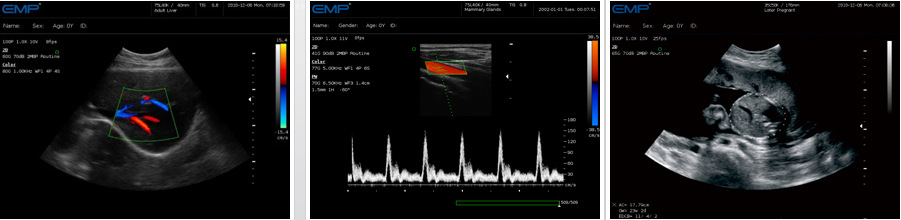

G60/G61是一款全身應用型彩色多普勒超聲診斷系統。該系統采用全數字化技術,配備瞭性能穩定可靠的

Linux操作平臺,整機造型輪廓優美,內部結構合理、貼膜工藝先進、操作舒適,圖像細膩真實,能夠滿足臨床多領域的診斷需求。

● 彩色多普勒(CFM) ——實時無創顯示區域血流信息,檢測客觀精確

● 頻譜多普勒(CW/PW) ——PW準確分析定點血流速度,精確提供距離分辨力;CW實時測量高速血流,優越的速度分辨力

● 優秀的3D成像 ——以更加生動形象的方式提供更多臨床重要的信息